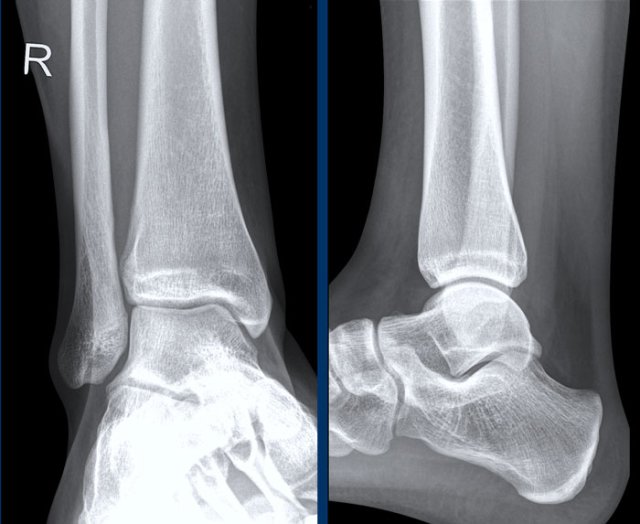

case 2 - ankle distortion

What are the findings and what does it mean?

Click on image for larger view.

Go to the discussion...